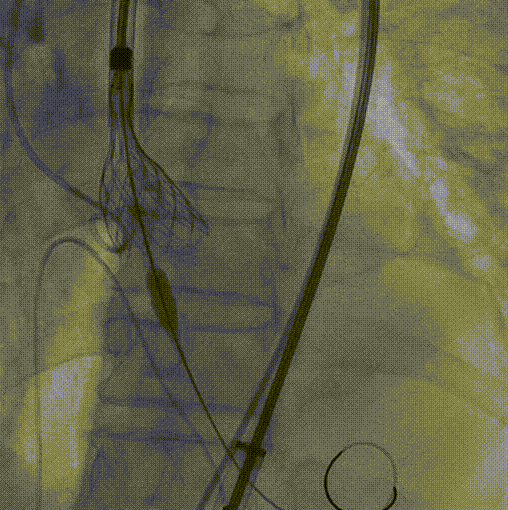

1.根据术前测量分析,采取右侧股动脉作为主入路,左股为辅入路,置入猪尾进行根部造影,造影可见主动脉根部瓣叶活动度低,冠脉灌注良好,少-中量反流。

根部造影

2.22mm球囊预扩,无明显腰征,冠脉显影良好,无造影剂渗漏。

22mm球囊预扩